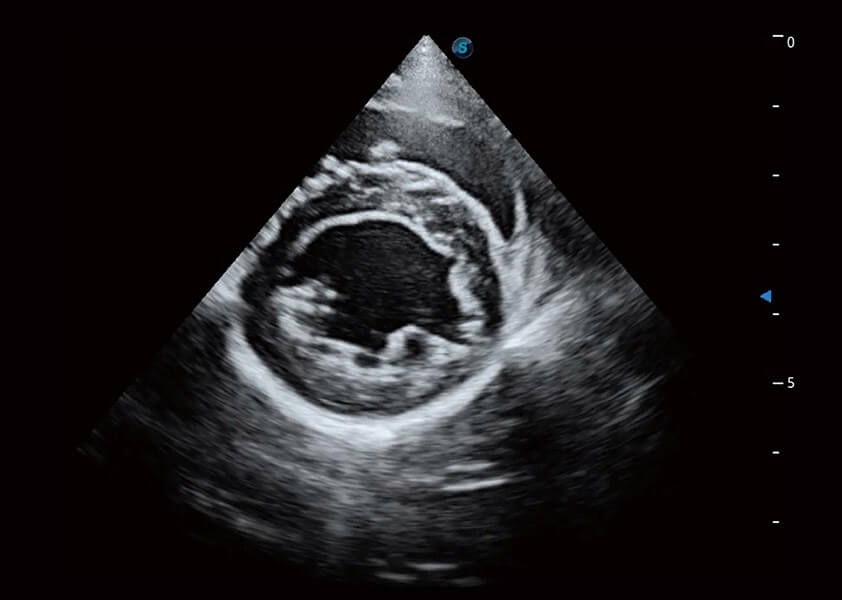

ProPet 60 作为一款高端台式动物超声设备,为动物医生的日常诊断提供了一系列贴合动物临床需求、解决临床实际问题的高级成像功能。凭借全系列高清探头,满足医生对腹部、心脏、生殖、浅表、肌骨等成像的所有需求,切实帮助您提升检查效率,提高诊断信心。